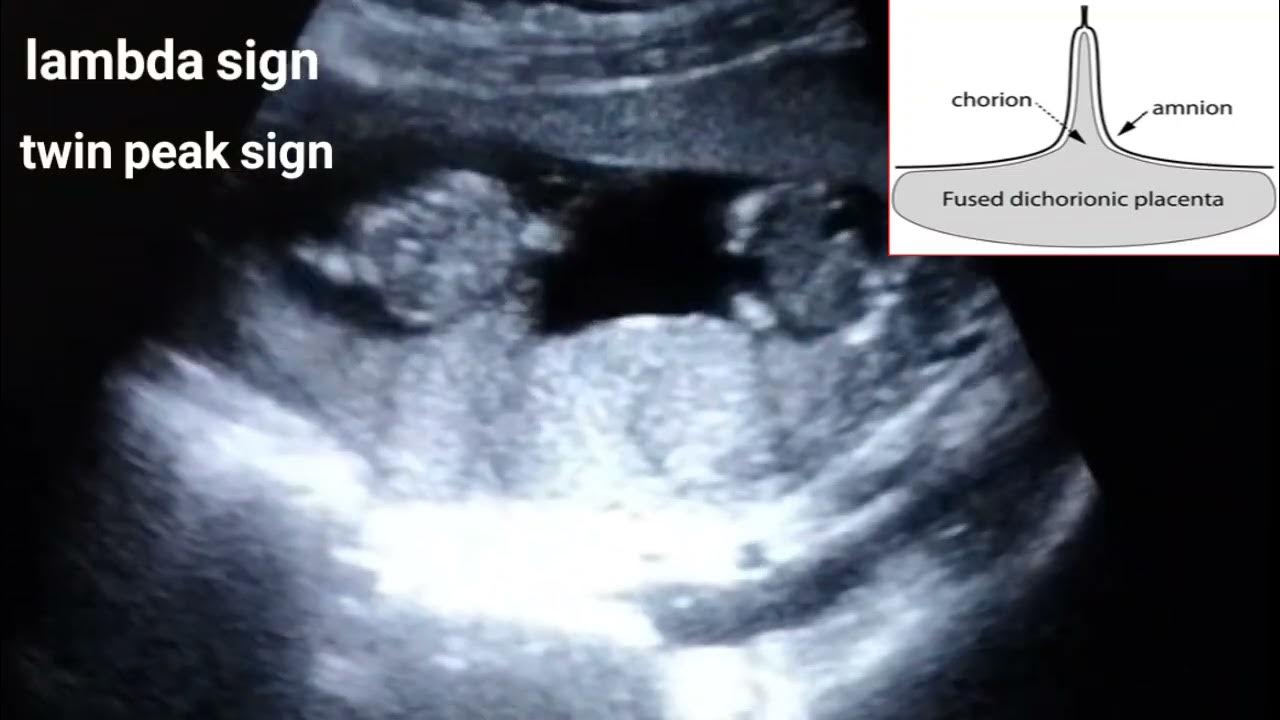

Lambda Sign Twins . evaluation of the twin peak or lambda sign in determining chorionicity in multiple pregnancy. the presence of the ‘lambda’ sign is believed to be the most reliable indicator for dd twin pregnancy with virtually. the twin peak sign, also known as the lambda (λ) sign, is the triangular appearance of the chorion insinuating between the layers of the. twin pregnancies and multiples in general are at higher risk for adverse pregnancy outcomes than are singleton pregnancies [1]. this document provides guidance on the role of ultrasound in the care of twin pregnancies, including screening, diagnosis and. If only 1 placenta is visualized, use twin peak sign vs. It is best seen on. Sepulveda w, sebire nj , hughes k et.al. Two placentas or differing fetal sex ⋄ dichorionic.

Lambda Sign Twins evaluation of the twin peak or lambda sign in determining chorionicity in multiple pregnancy. this document provides guidance on the role of ultrasound in the care of twin pregnancies, including screening, diagnosis and. It is best seen on. the twin peak sign, also known as the lambda (λ) sign, is the triangular appearance of the chorion insinuating between the layers of the. Two placentas or differing fetal sex ⋄ dichorionic. evaluation of the twin peak or lambda sign in determining chorionicity in multiple pregnancy. the presence of the ‘lambda’ sign is believed to be the most reliable indicator for dd twin pregnancy with virtually. Sepulveda w, sebire nj , hughes k et.al. twin pregnancies and multiples in general are at higher risk for adverse pregnancy outcomes than are singleton pregnancies [1]. If only 1 placenta is visualized, use twin peak sign vs.

Lambda And T Sign In Twin Pregnancy The lambda sign is also called Lambda Sign Twins If only 1 placenta is visualized, use twin peak sign vs. twin pregnancies and multiples in general are at higher risk for adverse pregnancy outcomes than are singleton pregnancies [1]. It is best seen on. the twin peak sign, also known as the lambda (λ) sign, is the triangular appearance of the chorion insinuating between the layers of. Lambda Sign Twins.